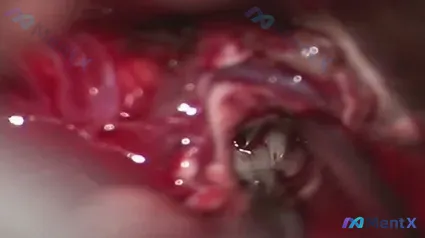

2019年术中血管镜见灰白色病灶:你的第一判断是什么?(附完整多模态分析路径)

整理了一个几年前的术中影像病例,觉得对血管镜下灰白病灶的鉴别挺有启发,分享一下思路。

- 时间:2019年10月16日术中

- 关键发现:血管内窥镜下见灰白色病变

- 影像背景:视野内可见金属支架结构,周围有红色血液成分,局部并非完全无血冲洗视野

影像特征拆解(先看直视下的关键点)

- 管腔与器械:中心见血管镜镜头前端,金属网状支架结构清晰,部分梁呈高亮反光

- 灰白灶细节:中央偏右下方血管壁见灰白、质硬、表面不光滑区域,缺乏正常内膜光泽

- 支架关系:需注意病灶是在网眼内还是支架外(这对后续定性很关键)